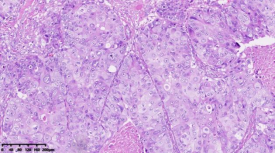

在本项研究中,研究人员利用基本的组织形态学方法及免疫组织化学法对TNBC进行分型:腔面雄激素受体型(LAR)(图1A),免疫调节型(IM)(图1B),基底样免疫抑制型(BLIS)(图1C),间充质型(MES)(图1D)。评价各亚型临床病理参数(如发病年龄、肿物大小、淋巴结转移等),组织形态学(肿物中央瘢痕形成、浸润模式、肿瘤间质浸润淋巴细胞、细胞排列方式、细胞核形态、核分裂计数、间叶化生等)以及免疫表型(p53、Rb、PD-L1、MMR等),结果显示:1.TNBC分型的临床病理、组织形态学和免疫表型特征不尽相同,有望成为复杂的基因表达谱分析的替代选择,为TNBC的分型治疗及靶向治疗提供理论依据;2.生物标记物 PD-L1作为重要的生物学指标,对个体化治疗及免疫治疗有重要的临床指导价值;3.乳腺癌中dMMR作为一个低频发生事件,不太可能作为免疫治疗有效性的评估手段。该成果发表在Virchows Archiv期刊,题目为“Subclassifying Triple-Negative Breast Cancers and Its Potential Clinical Utility”。文章DOI为:10.1007/s00428-022-03329-0。

图1. 基于组织形态学及免疫组织化学标记物的TNBC分型